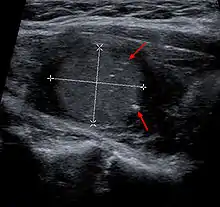

![]() Рак щитоподібної залози з мультифокальним ростом Рак щитоподібної залози з мультифокальним ростом | |

- Ультразвукове дослідження шиї, що дозволяє визначати злоякісні новоутворення від 3 мм в найбільшому діаметрі.